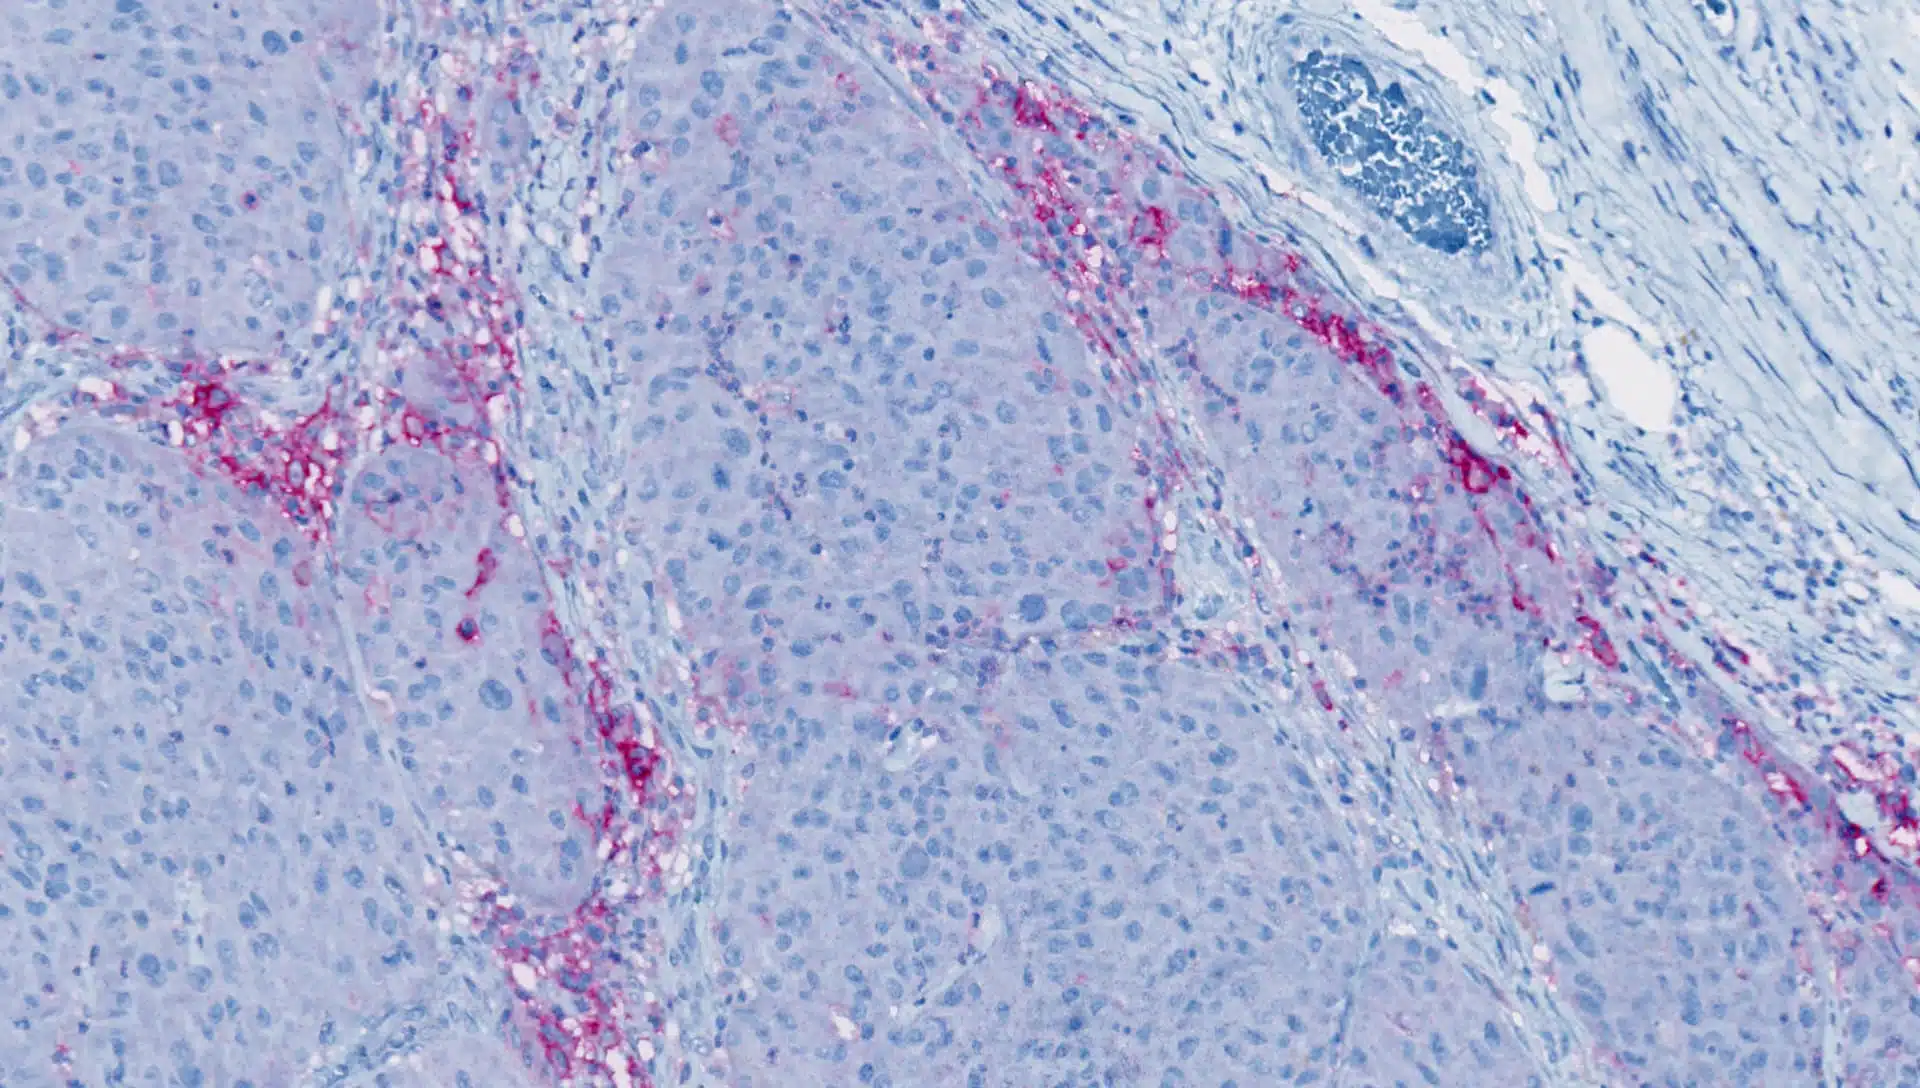

T-Regulatory IHC Multiplexの固体腫瘍分析検証

詳細な分析検証により、この堅牢なプロトコルが固形腫瘍組織に対して品質を保証します。

AACR 2022(アメリカ癌学会)で発表されたポスターをご覧ください